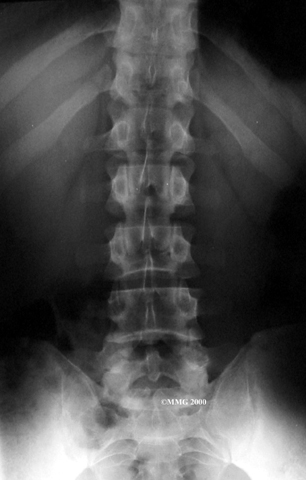

Physician Review

X-rays are of minor help in diagnosing disc herniations. The discs don't actually show up on X-rays. However, doctors can tell if the space between the vertebrae is smaller than normal. This can be an indication that wear and tear on one or more discs is causing problems. However, many peoples' X-rays show degeneration of the discs. This is because degeneration in the discs is part of aging, like skin that wrinkles with time.

X-rays